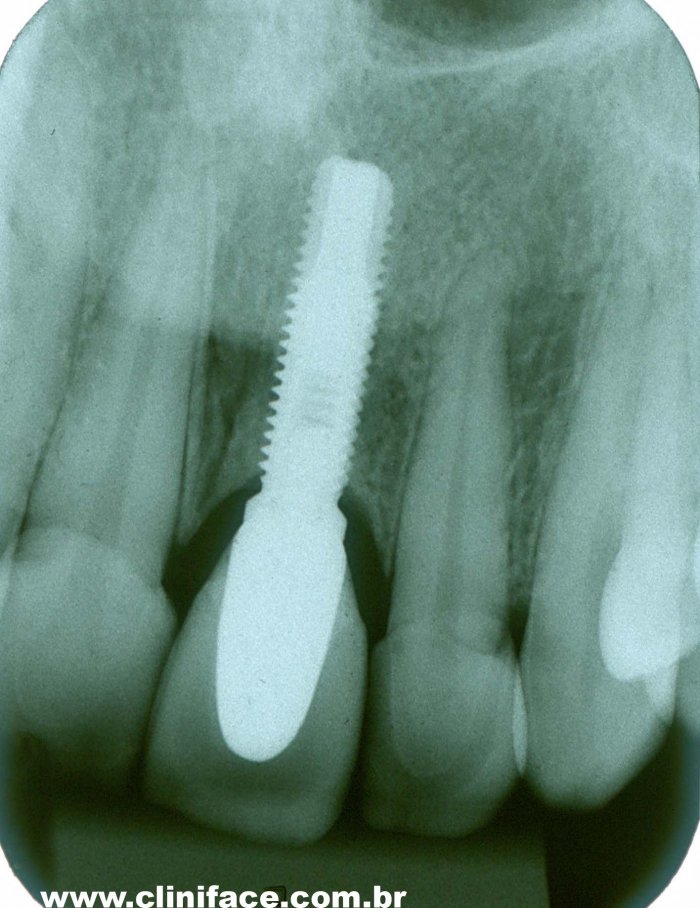

Raio X após a prótese instalada sobre implante